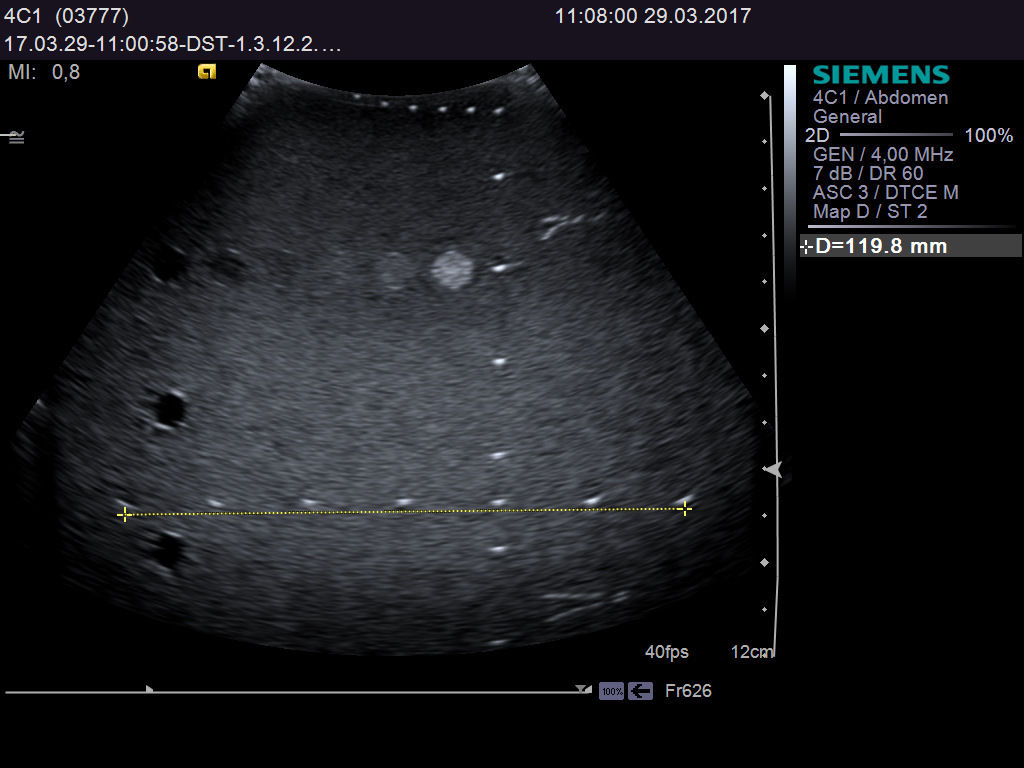

Understanding the Ultrasound Probe SIEMENS Acuson 4C1

The Ultrasound probe SIEMENS Acuson 4C1 employs cutting-edge imaging technology to provide high-resolution images that enhance diagnostic capabilities. It uses a linear array transducer, which allows it to capture detailed anatomical structures in real-time. This technology improves the clarity of the images, making it easier for healthcare professionals to identify and assess various conditions. Because of its advanced features, this probe is indispensable in ultrasound examinations.

Versatile Applications

This versatile ultrasound probe is suitable for a wide range of applications, including obstetrics, gynecology, and abdominal imaging. As a healthcare professional, you can rely on the Acuson 4C1 for both routine examinations and specialized procedures. The probe's design also ensures patient comfort during scans, which is crucial during sensitive examinations. Hence, it is widely used in hospitals and clinics around the world.